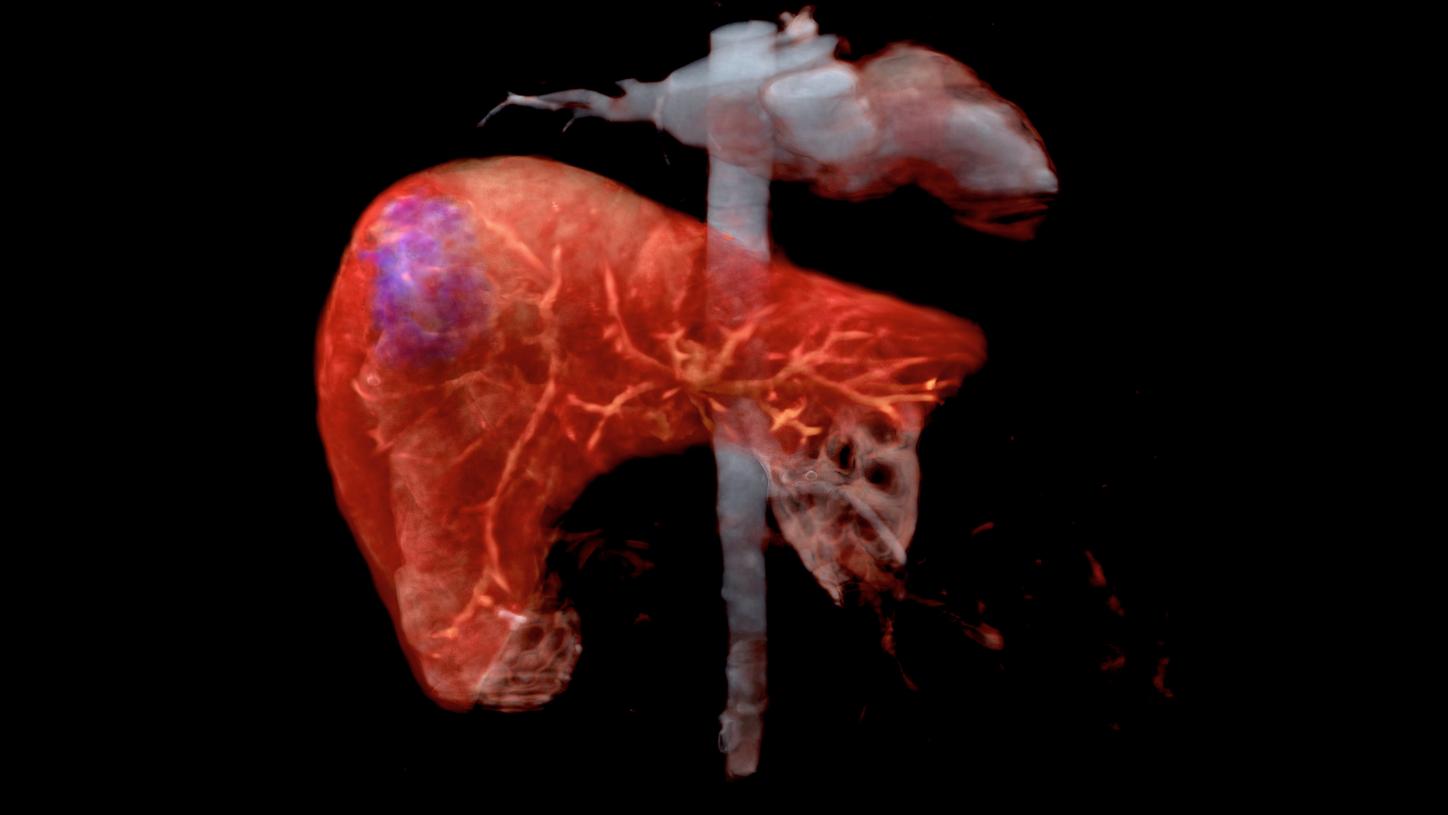

Navin PJ, Venkatesh SK. Hepatocellular Carcinoma: State of the Art Imaging and Recent Advances. J Clin Transl Hepatol. 2019 Mar 28;7(1):72-85. doi: 10.14218/JCTH.2018.00032